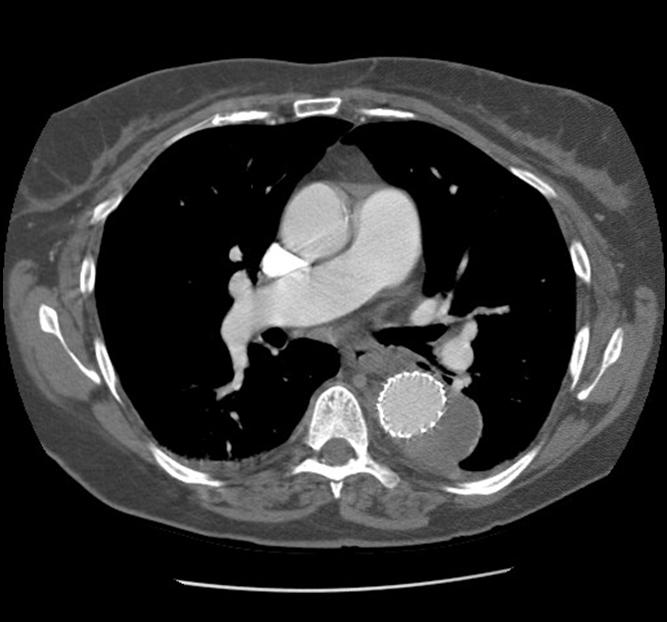

| Figure 2: Three dimensional reconstruction of the chest CT scan |

The patient was extubated in the operating room and moved all 4 extremities. He was observed in the Intensive Care Unit for 24 hours, but was able to sit in a chair in the evening of the day of his procedure. The patient commented that his back pain had completely resolved. On post-operative day 2, we obtained a contrast-enhanced high-resolution CT scan to check the position of the graft, and evaluate for endoleaks (Figure 3). The aneurysm was adequately excluded, and there were no evidence of endoleaks. A post-deployment three-dimension reconstruction of the chest CT was performed (Figure 4). The patient recovered uneventfully, and was discharged home on post-operative day 3. Subsequent follow-up has shown no evidence of aneurysmal sac enlargement.